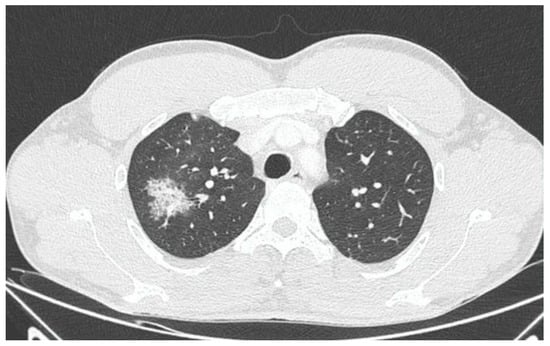

X-ray and CT scans of the chest were performed. The left lung’s lower lobe infiltrates and the right lung’s upper lobe interstitial changes (most probably of an inflammatory nature) were shown, as well as a small amount of fluid in the left pleural cavity (Figure 3 and Figure 4). Several tests were also performed to determine the etiology of the pneumonia. However, blood cultures, an antigen test for SARS-CoV-2, urine tests for Streptococcus pneumoniae, Legionella pneumophila, Cryptococcus sp., and Mycobacterium tuberculosis antigens, and an HIV screening test were all negative. In the following days, empirical antibiotic therapy with ceftriaxone and vancomycin was continued. A rapid improvement in the patient’s clinical condition was observed, as well as a significant decrease in the levels of inflammatory markers. On 22 August 2022, the patient was discharged home in good general condition.

Figure 4. CT scan of the chest showing right lung upper lobe interstitial changes during first hospitalization.

In this paper, we posed the question of whether there is a possible link between the initial infection and the subsequent occurrence of pulmonary disorders in the patient. Monkeypox viral pneumonia is one of the more commonly described complications of this disease in humans and can be associated with significant mortality [7,8,9,10,11]. Goff et al. published the results of an animal study (on primates), which concluded that monkeypox pneumonia can be lobular or interstitial pneumonia of viral etiology or can be caused by bacterial superinfection [10]. In the case we described, pneumonia occurred after the symptoms of the initial infection had already resolved and most likely was of bacterial etiology. Although it was not possible to identify any specific pathogen, bacterial etiology is supported by the overall clinical picture and, above all, the rapid resolution of symptoms after the administration of antibiotics. However, we cannot exclude the superposition of viral and bacterial pneumonia (in particular, bacterial superinfection of a primary viral infection). This possibility may be indirectly indicated by the heterogeneous radiological picture. In X-ray and CT scans, inflammatory lesions were visible in both lungs. However, while in the left lung, they were described as lobular pneumonia, in the right lung, there was an area of likely interstitial inflammatory lesions. It should be mentioned that the literature indicates that bacterial superinfection can exacerbate the symptoms of monkeypox viral pneumonia [10,12].